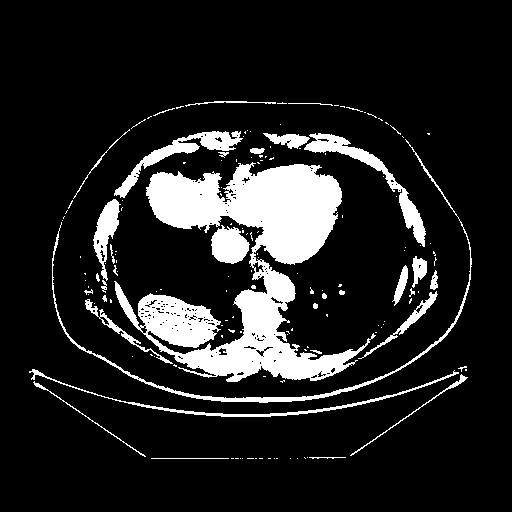

Original NATIVE CT scan (input)

Full window (WL 1023.5, WW 4095 β†’ Low βˆ’1024, High +3071)

Actual HU range: [-1024.0, 3071.0]